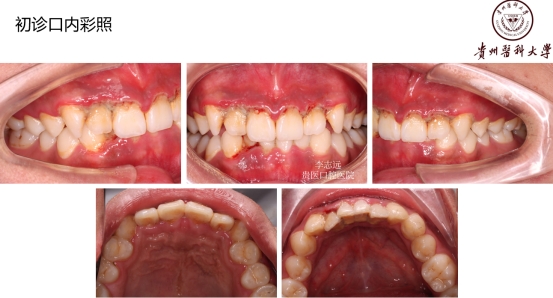

18岁,男性,经常抽烟,熬夜打游戏!!!

好发人群以及典型症状:该病好发于青壮年,多见于男性吸烟者、经常熬夜者、精神压力大者。得了这个病的话,前面描述的症状都可能会发生!牙龈的边缘及牙龈乳头发生坏死,常有黄白色假膜覆盖,很痛,有腐败臭味!!但是有这些症状时还是要小心另外一些很严重的疾病哦,比如白血病、艾滋等,得排除了它们,才能放心点。